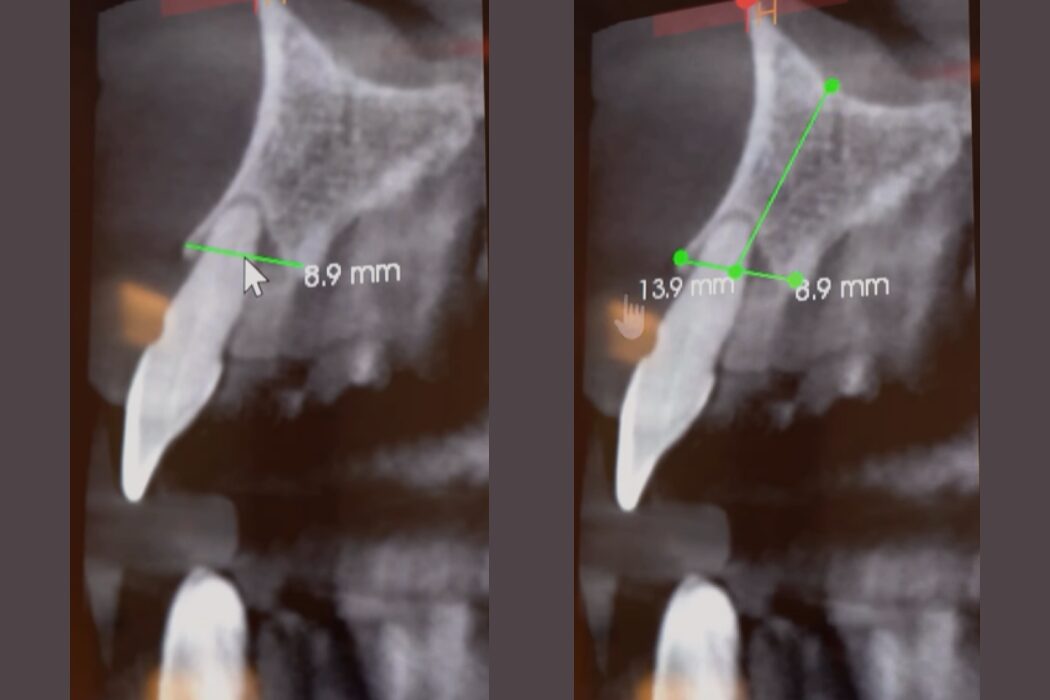

Un implante dental no es solo colocar un tornillo. Detrás hay diagnóstico, planificación y un proceso preciso para recuperar función y estética de forma estable.